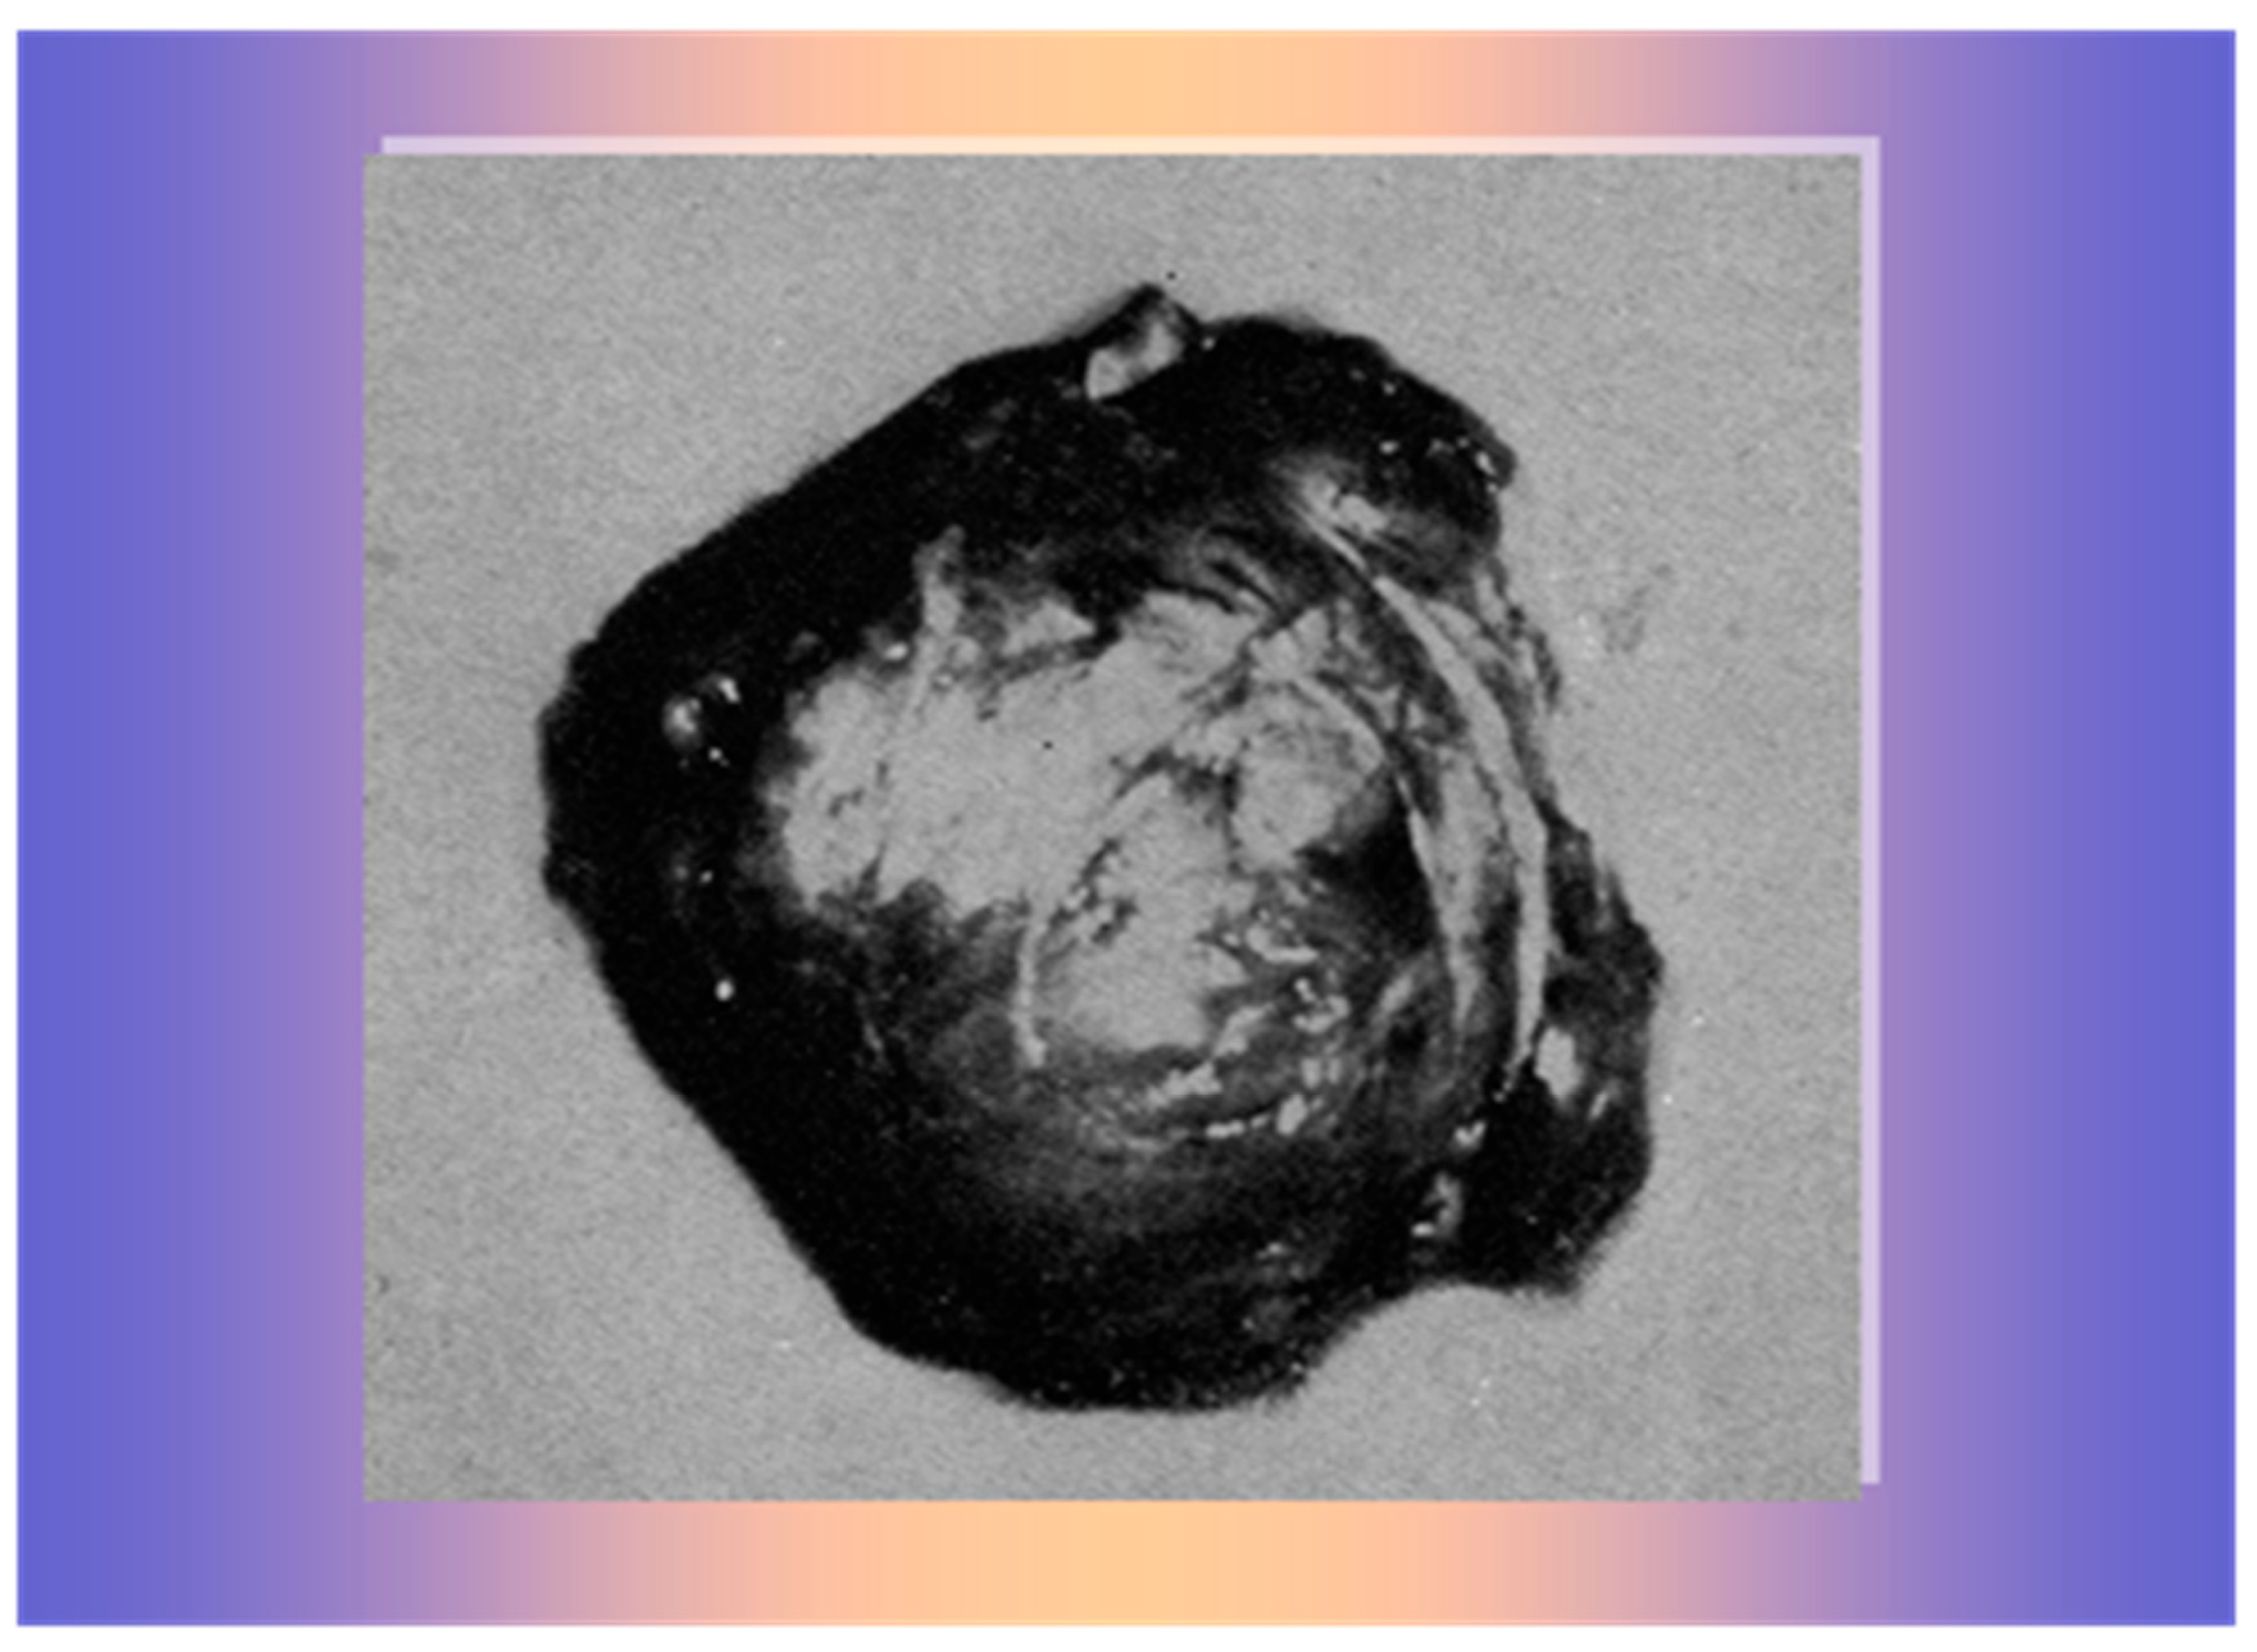

2. Case 1

3. Case 2